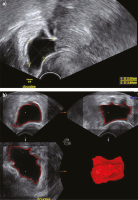

Abbildung 5a-b: „Wegklicken“ falsch aufgenommener Strukturen: (a) Im 3D-Bild befinden sich unten rechts eine rote, eine blaue und eine lila Struktur, die sicher nicht dem Ovar zuzuordnen sind. (b) Nach vorheriger Markierung und Druck auf die obere Trackballtaste wird jede dieser Strukturen weggeklickt, woraufhin ein plausibles 3D-Bild entsteht. Die Farben sind nun anders vergeben.

Abbildung 6a-b: Volumenberechnung von (a) freier Flüssigkeit im Douglas’schen Raum mit (b) Sono-AVC: Das Volumen wurde auf 26 ml kalkuliert.

Abbildung 7a-d: Befund bei eingebluteter Corpus-luteum-Zyste: (a) Zunächst wird die Zyste im größten Durchmesser gemessen. (b) Die echodensen eingebluteten Areale können bei Sono-AVC manchmal gewisse Unschärfen ergeben. (c) Im „Inverse Mode“ werden alle flüssigkeitsgefüllten Strukturen solide dargestellt und umgekehrt alle soliden Strukturen durchsichtig. (d) Die Zyste wird im Sono-AVC mit einem Volumen von knapp 25 ml berechnet.